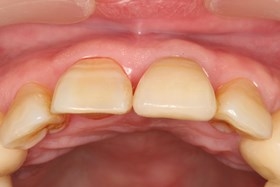

- 治療前全口X光片、口內正面照片。

治療前全口X光片、口內正面照片